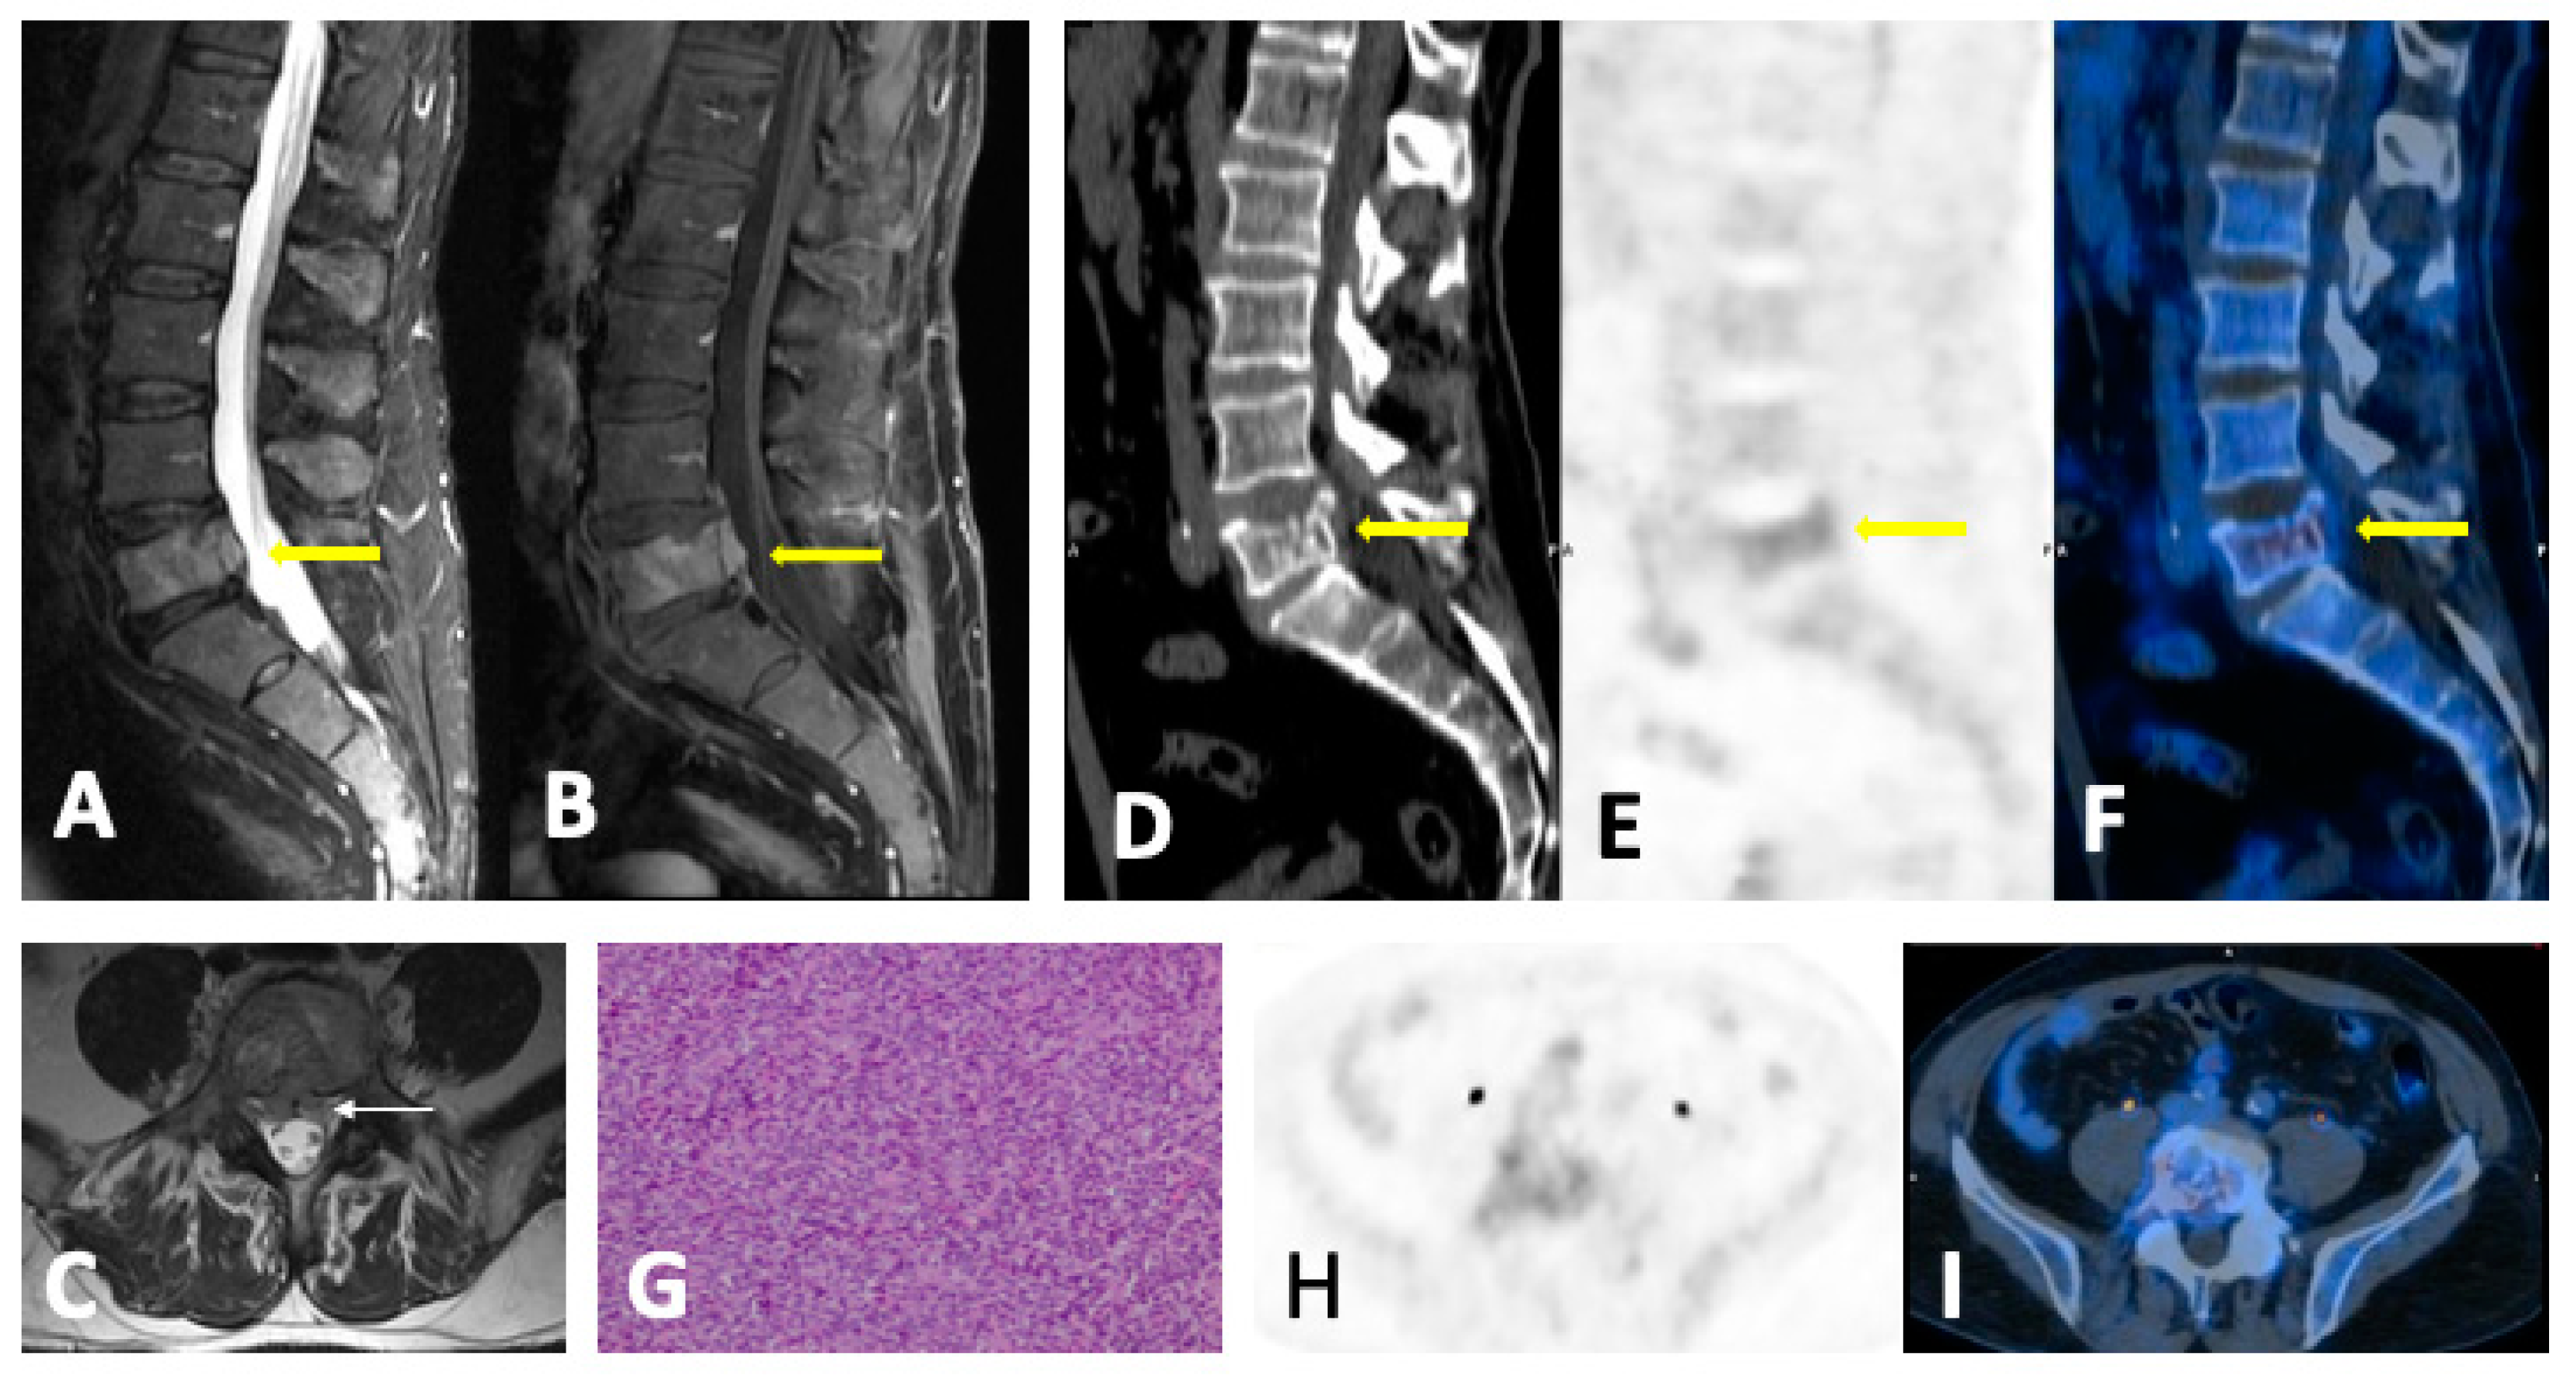

4.2. Disease Patterns

- Focal pattern: Focal myeloma infiltration was defined by circumscribed areas of high SI on STIR and T2WI. These corresponded to areas of low SI or, in a few cases, isointense signal upon an unenhanced T1WI [31]. The definition of focal lesion has evolved lately through the use of sequences such as DWI and Dixon. Therefore, focal lesions are defined as lesions greater than 5 mm hyperintense to background muscle at a b-value of 900 s/mm2, using ADC maps and confirming these findings with the corresponding Dixon sequences [32].

- Diffuse pattern: Diffuse disease can be suspected from a diffuse decreased signal on T1WI (either iso- or hypointense to intervertebral discs and muscle) and a diffuse increased signal throughout the marrow on T2FSWI, STIR, or high b-value DWI. Marrow ADC values above 600–700 μm2/s in a nontreated and newly diagnosed patient with MM could be used to increase confidence for the diagnosis of diffuse marrow involvement [33] (Figure 7). Due to potential false-positive findings, diffuse disease in imaging must be supported by bone marrow trephine biopsy [26].

4.3. Follow-Up Imaging Features